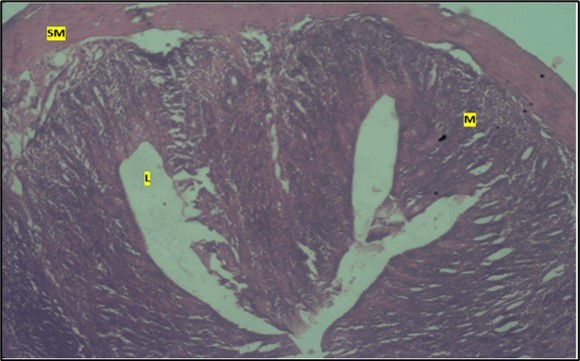

Histological examination of the small intestine result in control animals revealed a normal architecture with the red pulp and white pulp with no pathological observation Figure 2. Administration of Abelmoschus esculentus at low dose shows an increased cellularity with numerous cells in the Mucosa and the villi projecting towards the lumen. Focal metaplasia of mucosal cells alongside villous disruption was also observed (Figure 3). The high dose group showed normal cellular architecture with no villous disruption (Figure 4).

Figure 2.Control showing the mucosa with intestinal villi (v) projecting towards the lumen (l) and the underlying smooth muscle layer (sm) all appearing normal

Control showing the mucosa with intestinal villi (v) projecting towards the lumen (l) and the underlying smooth muscle layer (sm) all appearing normal